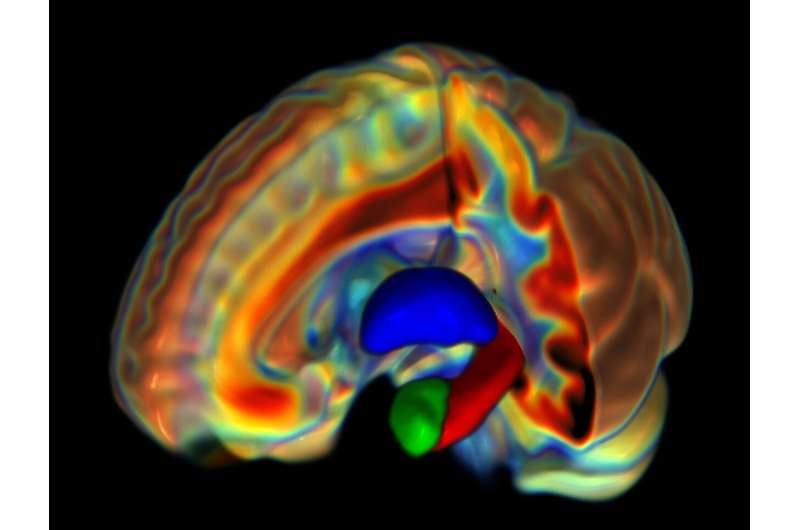

ساختار سلولی میکروسکوپی مغز یک زن بالغ که با استفاده از اِمآرآی اندازهگیری شده و تالاموس (آبی)، آمیگدال (سبز) و هیپوکامپ (قرمز) را نشان میدهد.

پژوهشگران برای تشخیص تفاوتهای جنسیتی احتمالی مغز زنان و مردان، نواحی ماده خاکستری زیر قشری (subcortical) از جمله آمیگدال (بادامه) و تالاموس را بررسی کردند که بنا بر پژوهشهای قبلی با سلامت روان مرتبط بودند.

سپس اسکن اِمآرآی مغز هزار و ۶۵ مرد و زن را بررسی کردند تا تفاوت در ریزساختار مغز، مانند نحوه متمرکز شدن سلولها، آرایش یا حتی ویژگیهای فیزیکی آنها را بیابند.

گروه پژوهشی یافته خود را تفاوتهای بزرگ و مرتبط با جنسیت در ریزساختارها توصیف کردند؛ همچنین دلیل تفاوت را در آمیگدال و تالاموس یافتند که احتمال میدهند با اختلالات روانی مانند اضطراب، کمتوجهیبیشفعالی، مشکل در مهارتهای اجتماعی و افسردگی مرتبط باشد.